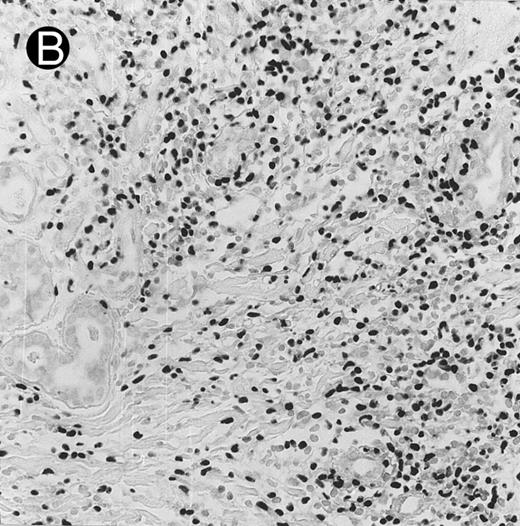

Histologically, the lymphomatous infiltrate was diffuse or patchy, with angiocentric and angiodestructive growth being observed in 30 cases (88.2%) (Figs 1 and 2). The cytologic composition was variable from case to case, including predominance of small cells, medium-sized cells, or large cells, or a mixture of these cell types (Fig 2 and 3). The tumor cell nuclei frequently showed irregular foldings and granular chromatin (Fig 2B). The larger cells possessed distinct nucleoli. The cytoplasm was moderate in amount and often pale. Karyorrhexis was usually prominent. Zonal tumor cell death, focal or confluent, was evident in 27 cases. In the 14 cases for which Giemsa-stained touch preparations were available, azurophilic granules could be identified in at least some of the neoplastic cells.

Cutaneous nasal-type NK/T-cell lymphoma (case no. 34). (A) This biopsy was initially misinterpreted as vasculitic lesion because of the small size of the lymphoid cells and the minimal cellular atypia. (B) Large numbers of lymphoid cells in the skin show positive labeling for EBERs on in situ hybridization. The sweat gland in the left field is negative.